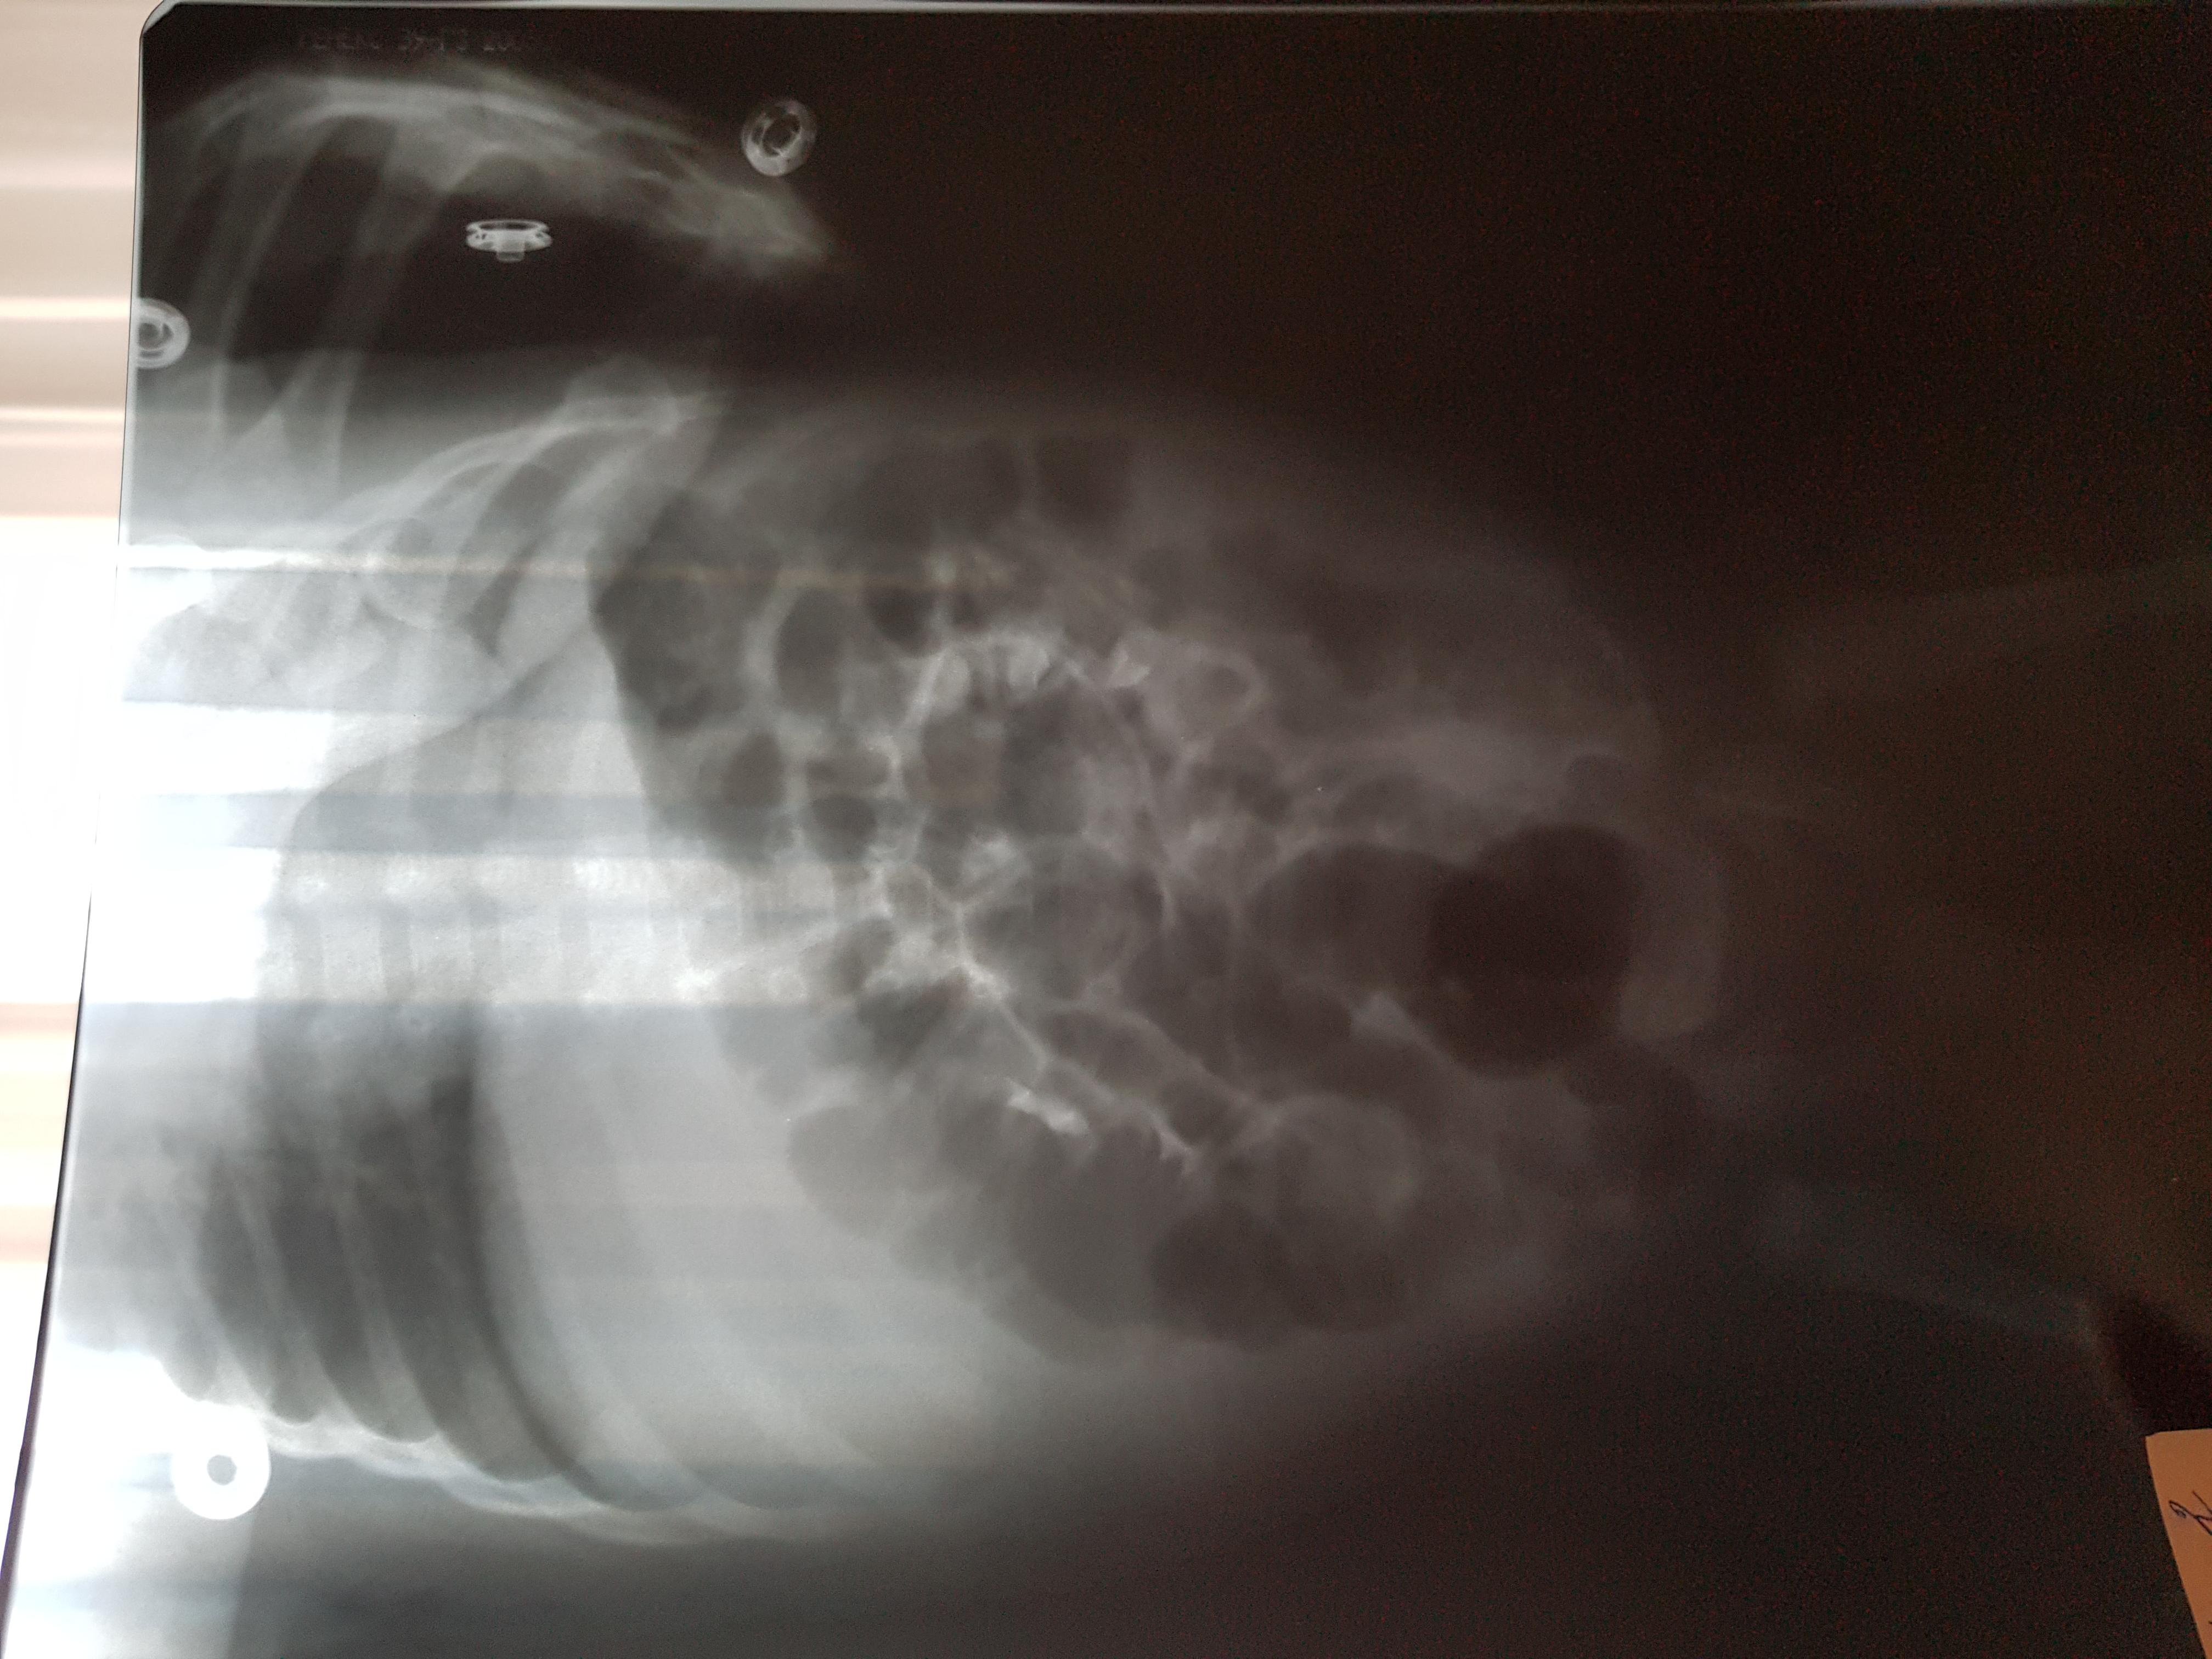

Болезнь Ормонда (ретроперитонеальный фиброз, забрюшинный фиброз) – хроническое воспаление жировой клетчатки забрюшинного пространства, которое постепенно приводит к компрессии и нарушению проходимости трубчатых структур данного анатомического участка. Чаще всего, в качестве этих тубулярных структур выступают мочеточники.

У меня есть сомнения, что причиной гидронефроза в Вашем случае явилось именно это состояние.

Возможно речь идет о пузырно-мочеточниковом рефлюксе.